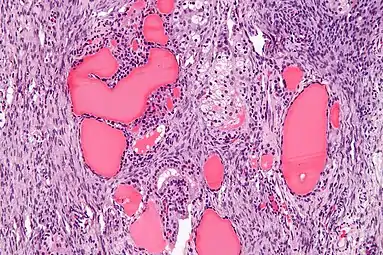

Micrograph of a struma ovarii. Characteristic thyroid follicles are seen on the right, and ovarian stroma on the left. H&E stain. | |

- High magnification Struma ovarii